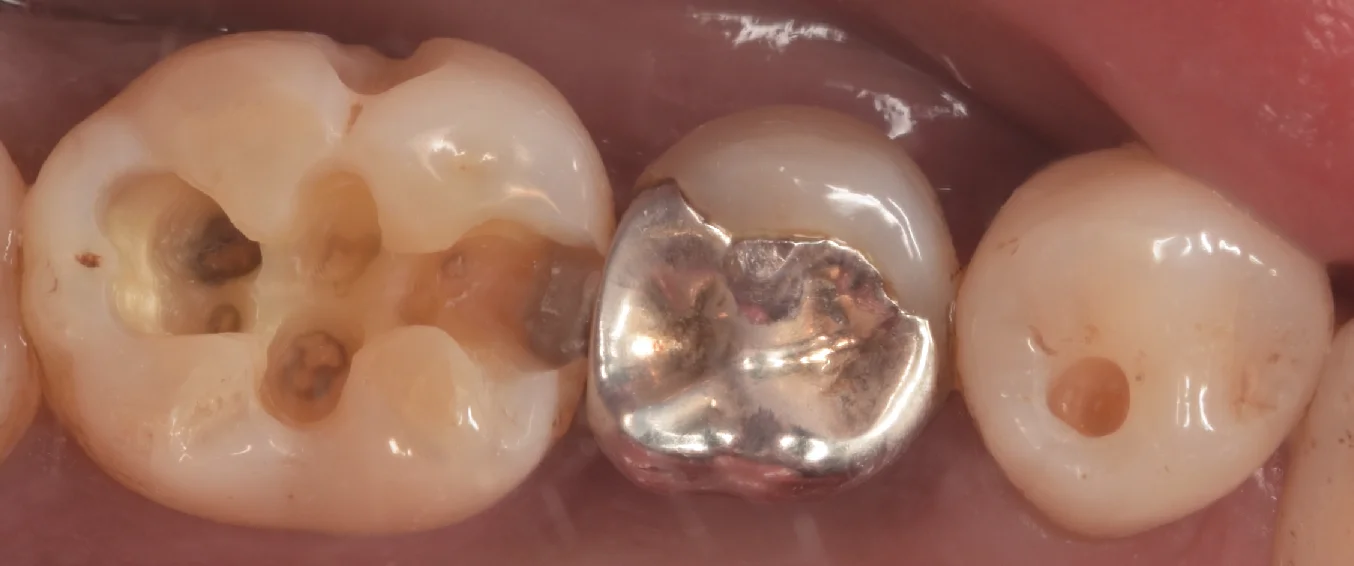

まずは術前からです。

今回は、画面上の左側の金属(アマルガム)と一番右の黒く穴が空いている場所を治療していきます。

アマルガムは随分と昔に日本市場から消えた材料です。

私が毎回行っているダイレクトボンディングなどの台頭に伴い国内では完全に消え去った治療になります。

この材料は水銀を固めて歯に詰めているものになります。

水銀と聞くと警戒してしまいそうですが、この状態では基本的に水銀が溶け出したりして体に害が生じることはないと言われています。

またダイレクトボンディングと違って膨張していく材料になるため、隙間ができづらく虫歯にはなりづらいとされていますが、歯にクラックという亀裂が生じやすくなってしまうのがデメリットです。

また実際にはこの写真のようにアマルガムが欠けたりすることで大きくギャップができてしまい、そこから虫歯になることが多いです。

なんの問題もないのであれば積極的に除去する必要はないかと思われますが、虫歯になっているのであれば治療に入った方が無難だと思います。

アマルガムを除去し、右の歯の虫歯を見やすくしたのがこちらになります。

左の歯の内部が真っ黒になっており、右側の歯についてもそこそこ内面が黒く広がっているのがわかるかと思います。